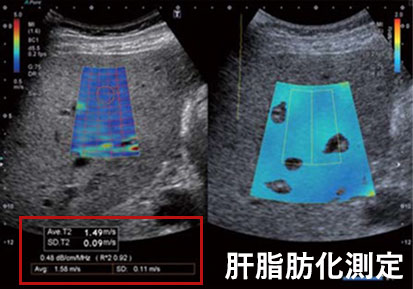

肝脂肪化測定では、エコーの減衰を数値化できる最新技術で肝脂肪化の程度を計測します。

脂肪が肝臓へ推積すると超⾳波が通りにくくなる特徴(減衰)を利⽤して、肝脂肪化の程度を客観的な”数値“で把握できるようになりました。

肝脂肪化測定

客観的な”数値“で把握